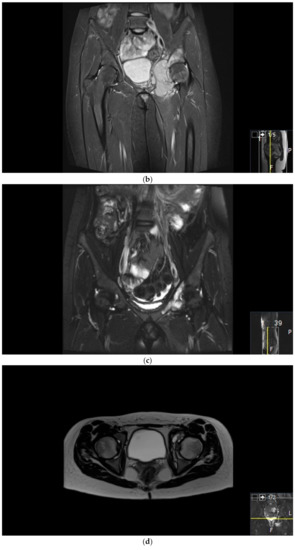

Figure 2.

Surgical failure of biological reconstruction after major pelvic surgery, salvaged with endoprosthesis. (a,b) A previously healthy 15-year old girl with 1-year history of left-sided groin pain. MRI of the pelvis (T1 TIRM coronal (a) and axial (b) images) showing a bone tumor involving the left superior ramus of the pubic bone and the periacetabular region of the iliac bone. There is a soft tissue component engaging the obturator internus-externus and adductor muscle. Staging procedures did not show any evidence of metastatic disease. Fine-needle aspiration showed a monotonous small round blue-cell tumor most likely representing Ewing sarcoma. FISH analysis showed an EWSR1-Fli1 fusion transcript confirming the Ewing sarcoma diagnosis. (c,d) After induction chemotherapy with VIDE (vincristine, ifosfamide, doxorubicin, and etoposide), the soft tissue component, as well as the intraosseous extension of the tumor, was significantly reduced, as shown on the coronal (c) and axial (d) T2 TSE FS MRI images. (e) The patient underwent a P2/P3 internal hemipelvectomy, extra-corporeal irradiation with 55 Grey and re-implantation of the autograft. (f,g) One year after primary surgery, the autograft collapsed (f), requiring salvage reconstruction with the Mutars Lumic Cup (g). A year later, the patient is functioning well and remains free of disease.